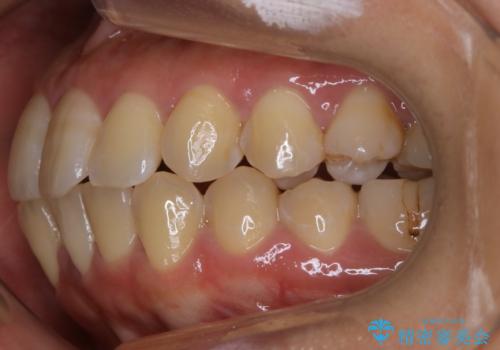

抜歯を行うことで前歯を後ろへ下げるスペースを獲得し、口元の突出感や歯のガタつきを改善していきました。

- 前歯を後ろへ下げることを主訴に来院された患者様です。

口元の突出感の改善や歯の移動量などを考慮し、抜歯を伴うワイヤー矯正での治療を選択しました。